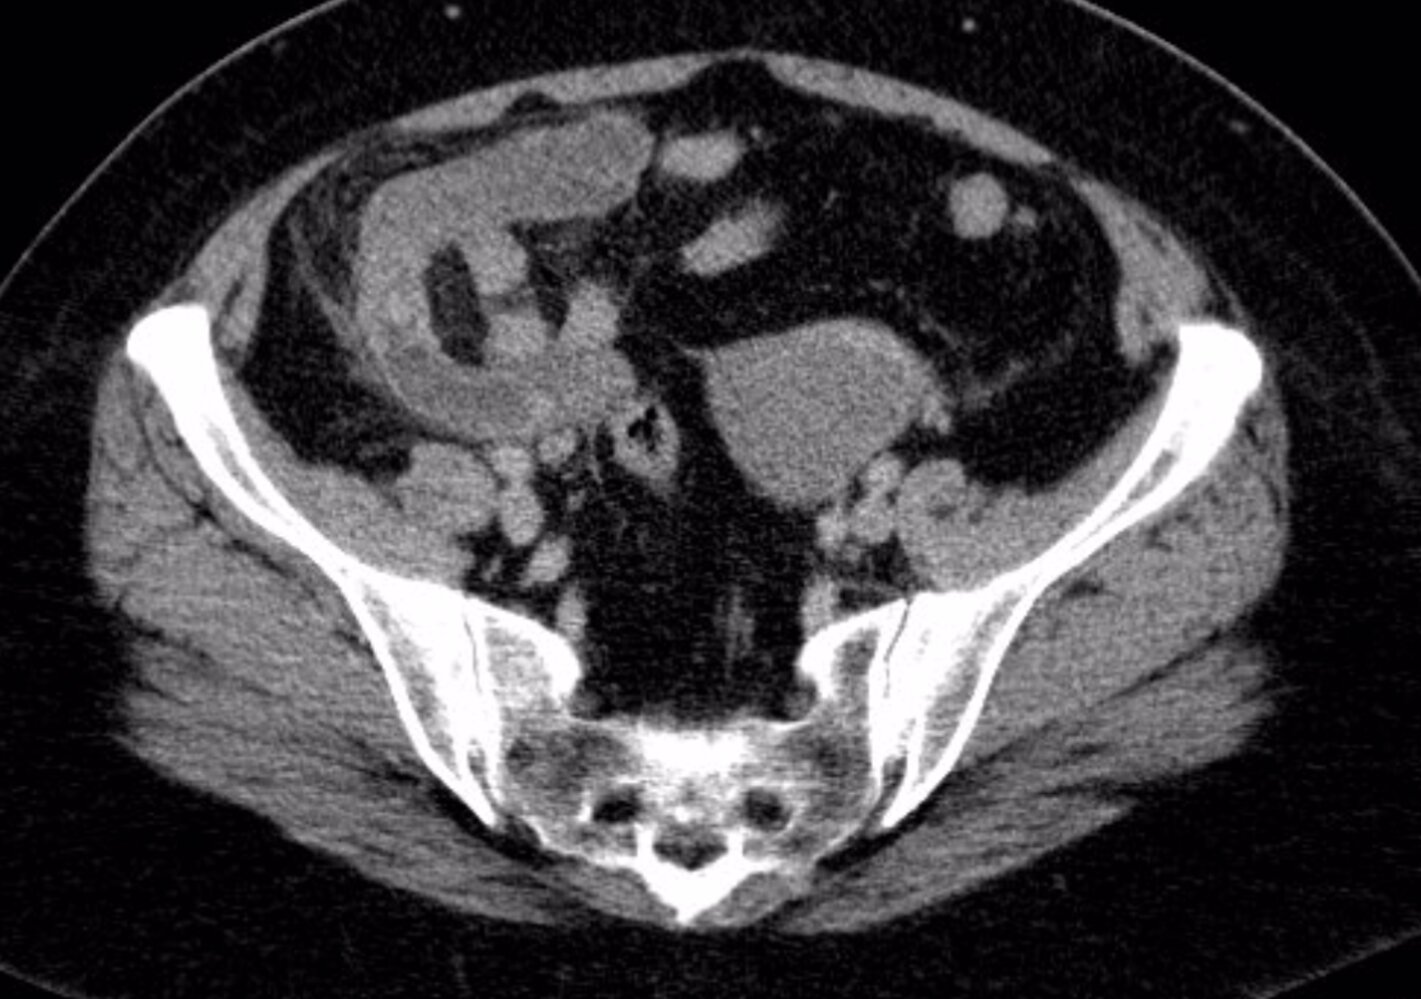

CT abdomen with IV contrast

CT abdomen is the most accurate initial imaging modality for appendicitis. [12][29]

Supportive findings [29]

- Distended appendix (diameter > 6 mm)

- Edematous appendix with periappendiceal fat stranding

- Possible appendiceal fecalith: focal hyperdensity within the appendiceal lumen

- Evidence of complications

- Consider low-dose CT scan (with IV contrast) to minimize radiation exposure. [33][34]

- Consider CT without contrast in patients with contrast allergy. [34]

Adding oral and/or rectal contrast does not improve diagnostic accuracy and may delay diagnosis. [10]